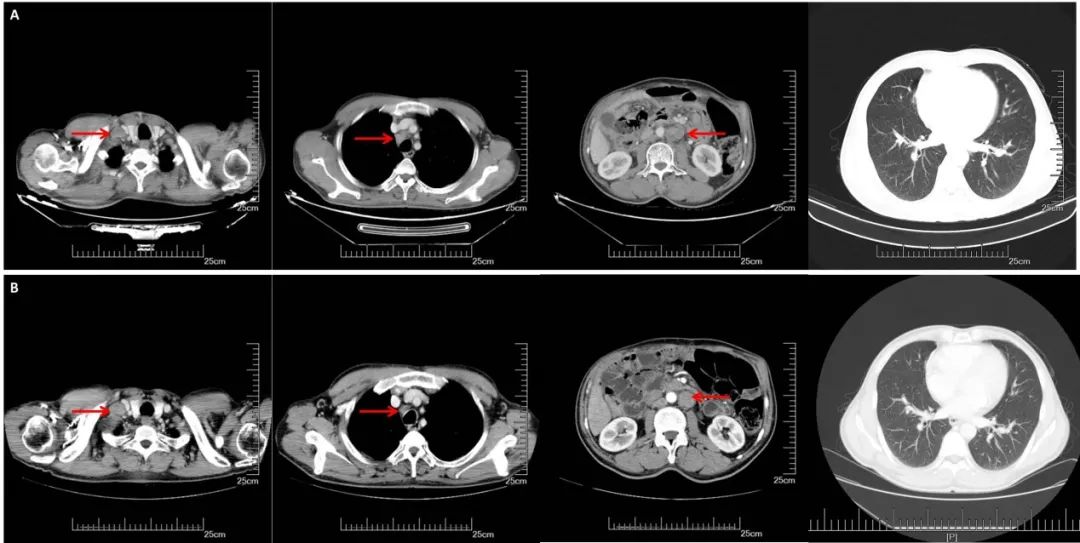

A:CT增强(2018.11.07): 腹膜后多发淋巴结转移,部分较前增大。双侧锁骨上淋巴结转移,部分较前增大,双肺多发结节,转移可能;B:CT增强(2019.05.16):腹膜后淋巴结较前缩小,双肺转移较前增多增大;C:CT增强(2019.10.25):腹膜后淋巴结稳定,双肺转移较前增多增大;D:CT增强(2020.05.27):双肺转移瘤及腹腔淋巴结总体稳定。